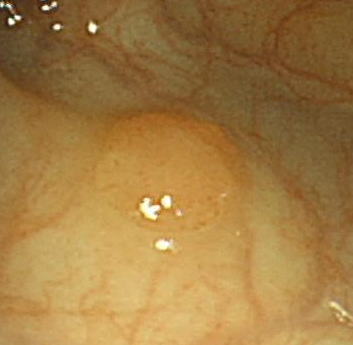

NBIは内視鏡で血液に強く吸収される特殊な狭い波長の光(415nmと540nm)のみを照射し、消化管粘膜を観察します。毛細血管が豊富な早期がんのごく小さな粘膜でも感度良く見つけることができる画期的なシステムです。

特に、平坦な早期がんの多い食道では、従来色素内視鏡といって、ヨードを食道に吹き付け染色し観察する方法が行われていましたが、大変時間もかかり、苦痛も多く一般診療では困難とされていました。この方法では内視鏡のスイッチ一つでヨードを用いることもなく簡便に色素内視鏡と同じような検査が可能となりました。食道以外も、胃や大腸でもNBI観察は大変有効です。

【大腸のポリープ 左が通常観察 中央が従来の色素観察、右がNBI観察です 】